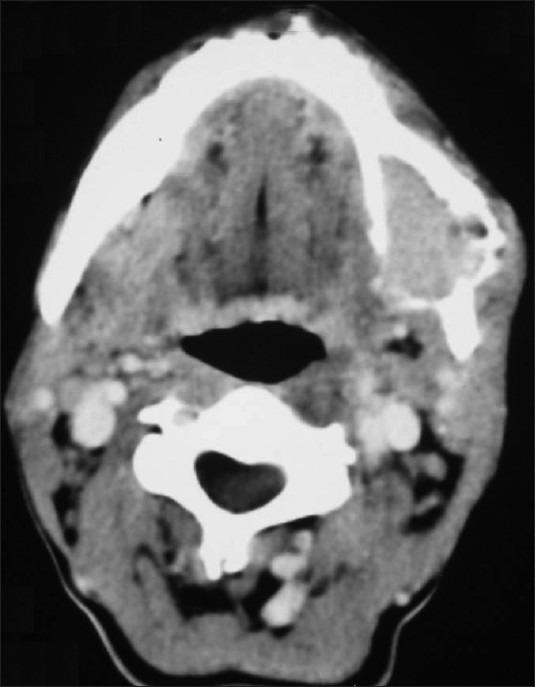

Mandibular metastasis due to thyroid carcinoma is not very frequent and the cases described in the literature are few. Due to its bloodstream dissemination, most of them are a consequence of the follicular variant of thyroid carcinomas. We are presenting a case in which the metastatic lesion of mandible was detected before diagnosis of primary malignancy.